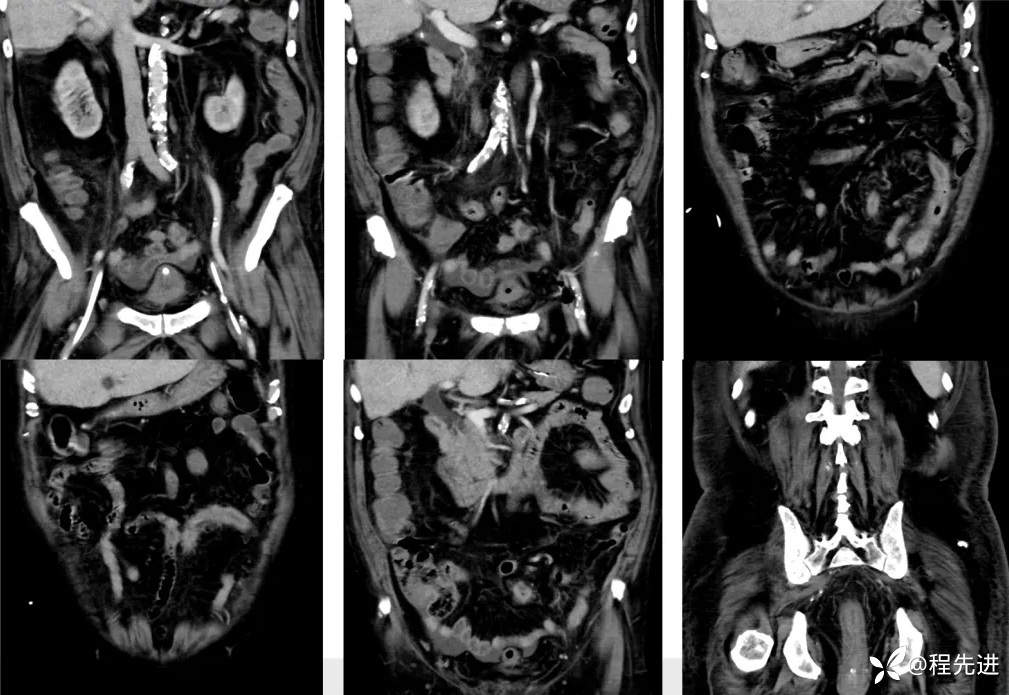

影像检查: